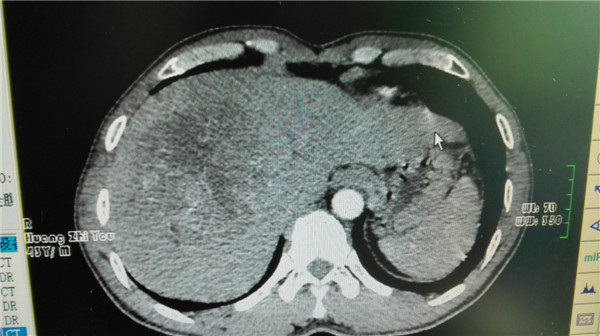

• 大肝癌未必只能“坐以待毙”

大肝癌未必只能“坐以待毙”

肝癌素有“急性癌”之称,起病隐匿、发展快、预后差。大肝癌是指肿瘤直径5cm的肝癌,而巨大肝癌则是指肿瘤直径10cm 的肝癌,两者约占临床确诊肝癌...